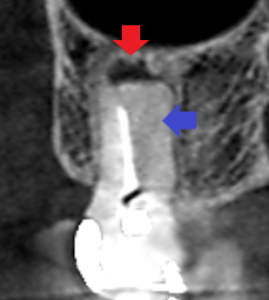

精密根管治療6カ月後の経過観察時の矢状断のCT画像です。

未治療だった遠心頬側根も根の先までしっかり根管充填され、

矢印の先の根の先にあった膿の影が消失し、歯槽骨が再生しています。